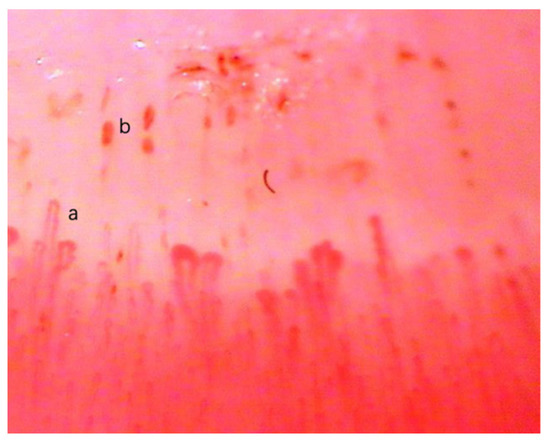

3.1. Data Collection and Preprocessing